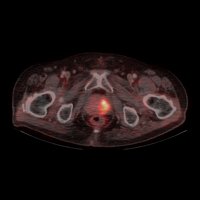

PET/CT vyšetrenie s 68Ga-PSMA

Diagnostika karcinómu prostaty